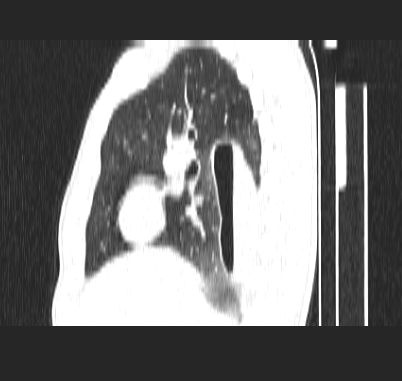

标题: CT19170:男 24岁,胸部外伤一周行CT检查 [打印本页]

男 24岁,胸部外伤一周行ct检查 未传纵隔窗

结合病史考虑肺挫伤后所致的肺气囊表现

考虑----右肺下叶背段包裹性液气胸

首先考虑肺裂伤形成的液气囊肿.纵膈胸膜包裹性的液气胸可能性小,病变主要在肺内.

壁光滑完整,周围未见炎性灶及粘连带,考虑肺囊肿,不一定跟外伤有关!

结合临床考虑为右肺下叶背段撕裂伤后形成局限性包裹性的液气胸。

有否先天性可能,病程仅一周,病灶周围实质无明显异常表现.